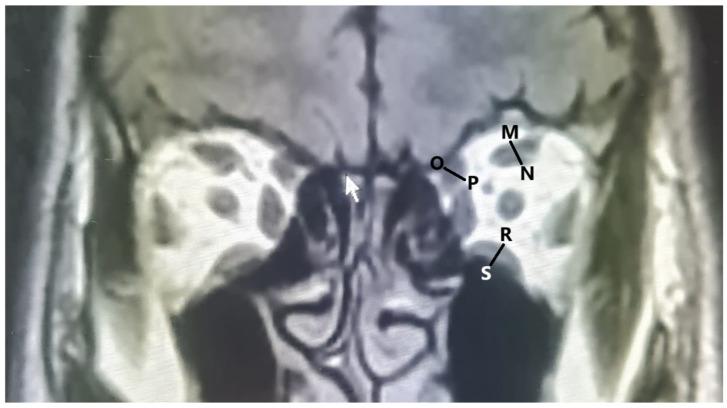

METHODS

RESULTS

The mean values of the diameters of the extraocular muscles in males and females were as follows: medial rectus, 3.96 ± 0.52 and 3.58 ± 0.53 mm; lateral rectus, 3.47 ± 0.61 and 3.15 ± 0.48 mm; inferior rectus, 4.47 ± 0.53 and 4.07 ± 0.48 mm; superior rectus, 4.44 ± 0.64 and 4.01 ± 0.56 mm; and superior oblique, 3.68 ± 0.49 and 3.45 ± 0.44 mm. The length of the interzygomatic line in males and females were 102.68 ± 3.89 and 96.95 ± 3.4 mm, the ocular bulb length was 23.33 ± 1.32 and 22.83 ± 1.1 mm, the globe position was 7.66 ± 1.33 and 7.3 ± 1.39 mm, and the width of the optic nerve sheath diameter was 4.65 ± 0.62 and 4.28 ± 0.51 mm, respectively. All measurements were significantly greater for males than for females ( < 0.05).

方法

在 102 名个体的 204 个眼眶的 T1 加权磁共振(MR)图像中,测量了眼外肌直径、视神经鞘直径宽度、眶间距离、眼球长度和眼球位置。

结果

男性和女性眼外肌直径的平均值分别为:内直肌,3.96 ± 0.52 和 3.58 ± 0.53mm;外直肌,3.47 ± 0.61 和 3.15 ± 0.48mm;下直肌,4.47 ± 0.53 和 4.07 ± 0.48mm;上直肌,4.44 ± 0.64 和 4.01 ± 0.56mm;和上斜肌,3.68 ± 0.49 和 3.45 ± 0.44mm。男性和女性眶间距离分别为 102.68 ± 3.89 和 96.95 ± 3.4mm,眼球长度分别为 23.33 ± 1.32 和 22.83 ± 1.1mm,眼球位置分别为 7.66 ± 1.33 和 7.3 ± 1.39mm,视神经鞘直径宽度分别为 4.65 ± 0.62 和 4.28 ± 0.51mm。所有测量值男性均显著大于女性(<0.05)。